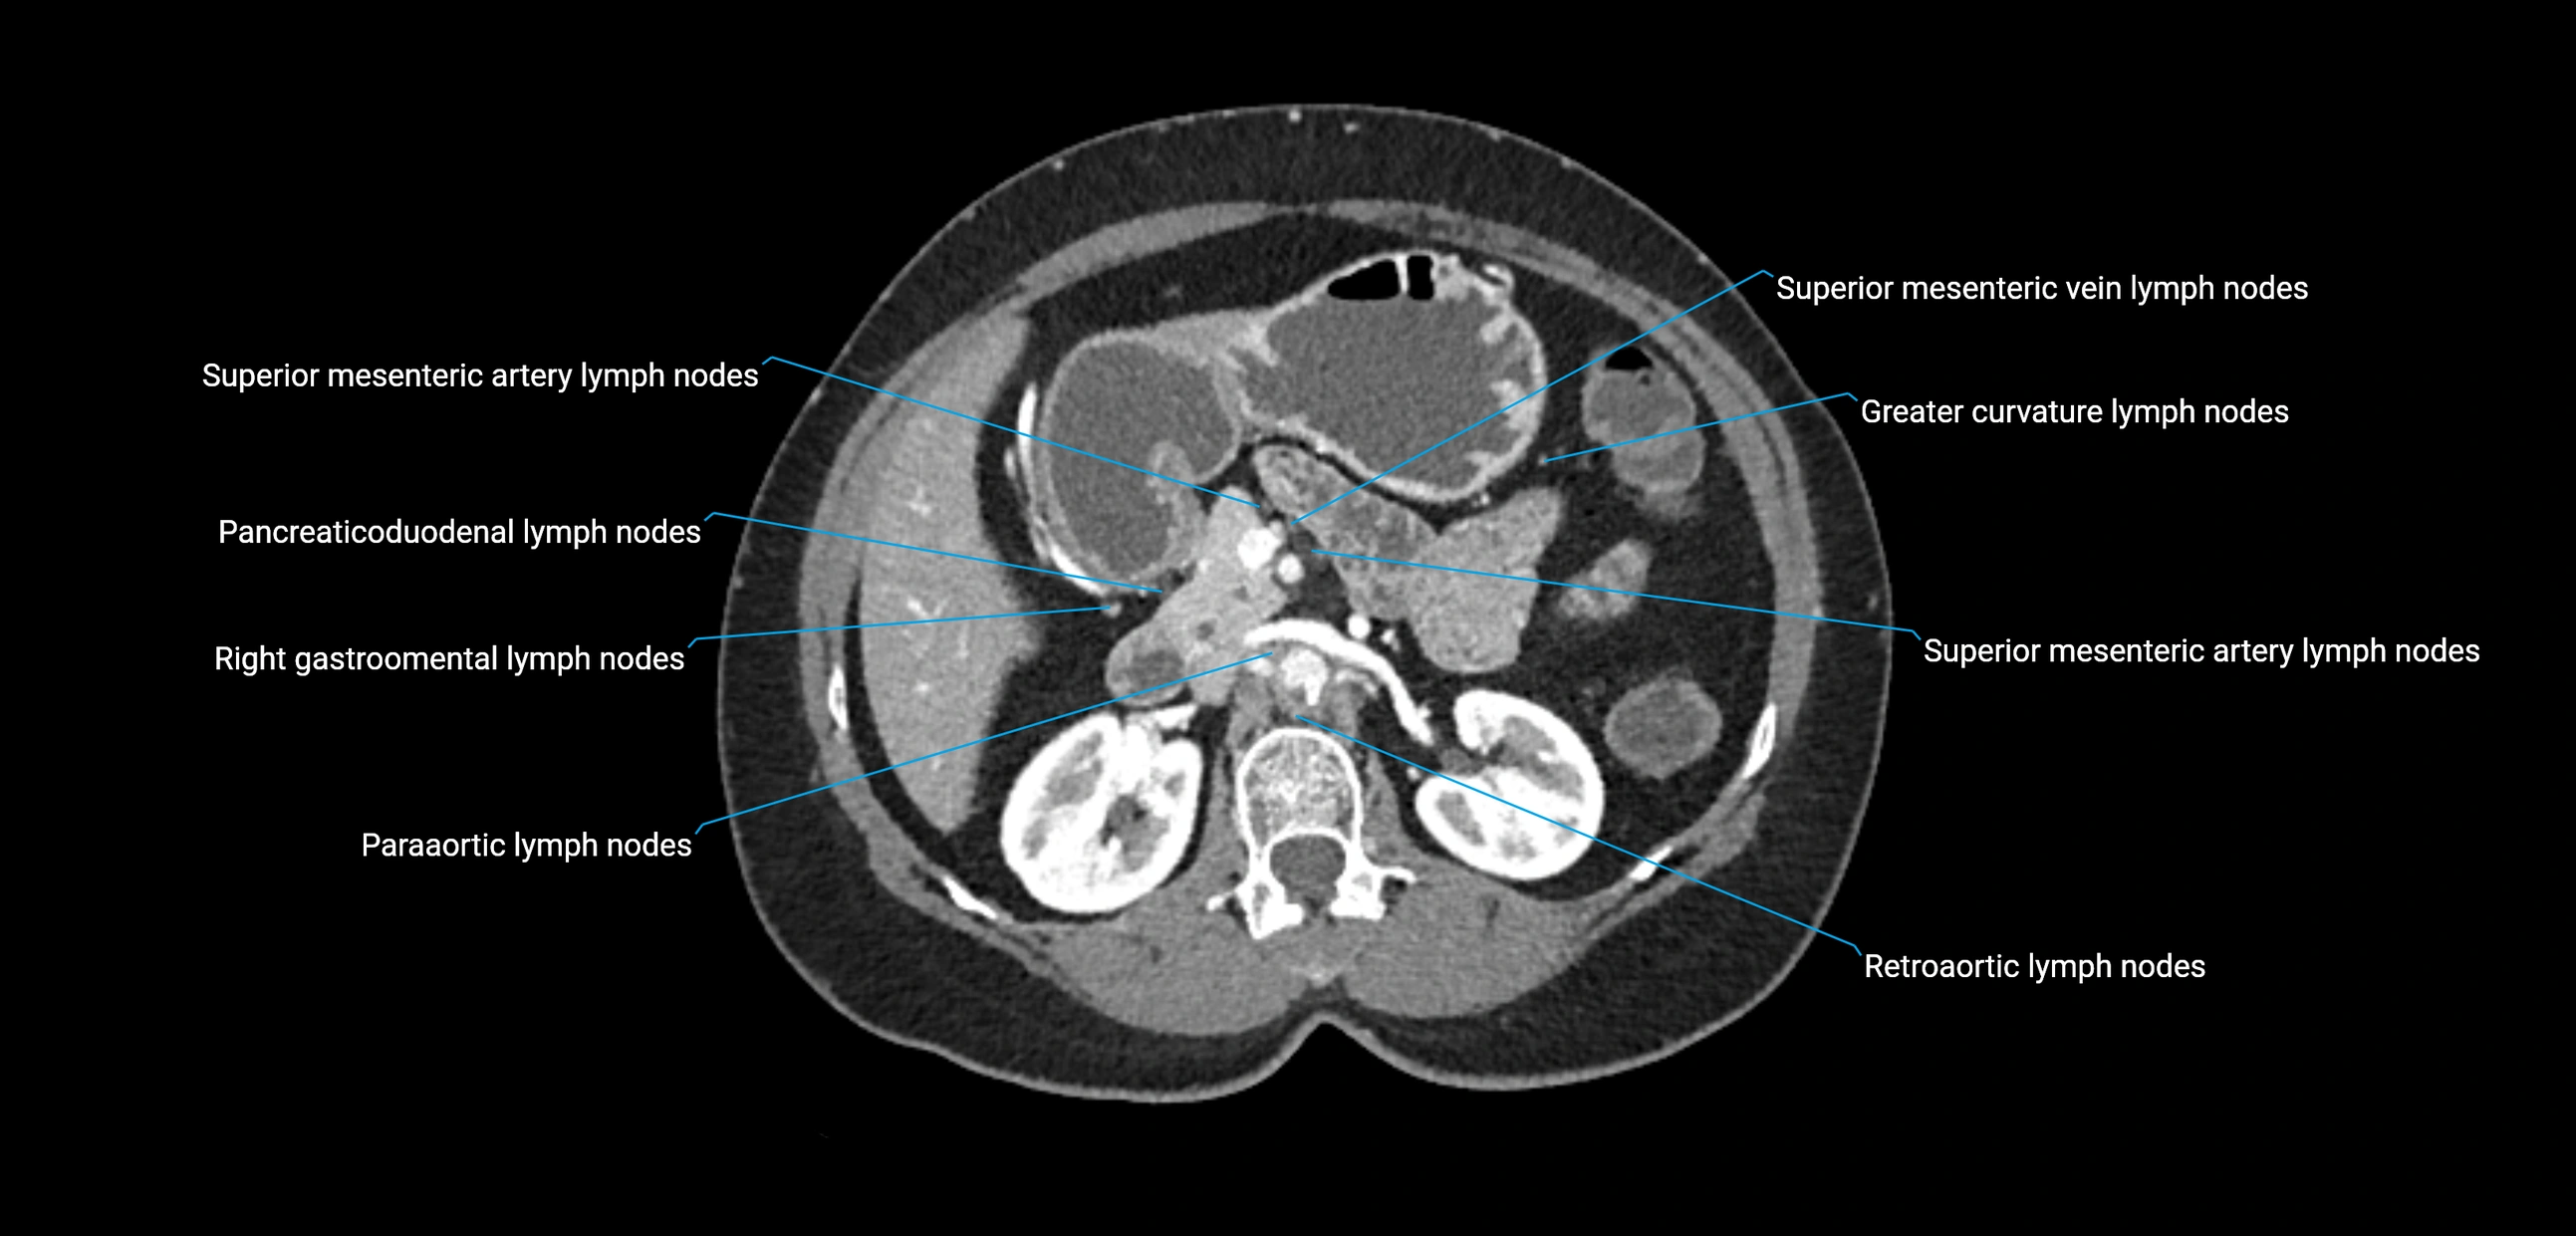

CT Appearance

CT Pre-Contrast:

• Nodes appear as soft-tissue density nodules adjacent to the aorta and IVC

• Calcification may be seen in chronic infections (e.g., tuberculosis)

CT Post-Contrast:

• Normal nodes enhance homogeneously

• Malignant nodes may show heterogeneous enhancement, central necrosis, or conglomerate formation

• Size >1 cm short axis is suspicious, though morphology and distribution are equally important

CT Venography (CTV):

• Demonstrates nodal encasement or compression of adjacent vessels (aorta, IVC, renal veins)

• Useful in staging testicular and ovarian malignancies

• Provides 3D reconstructions for retroperitoneal lymph node dissection planning

CT image

image